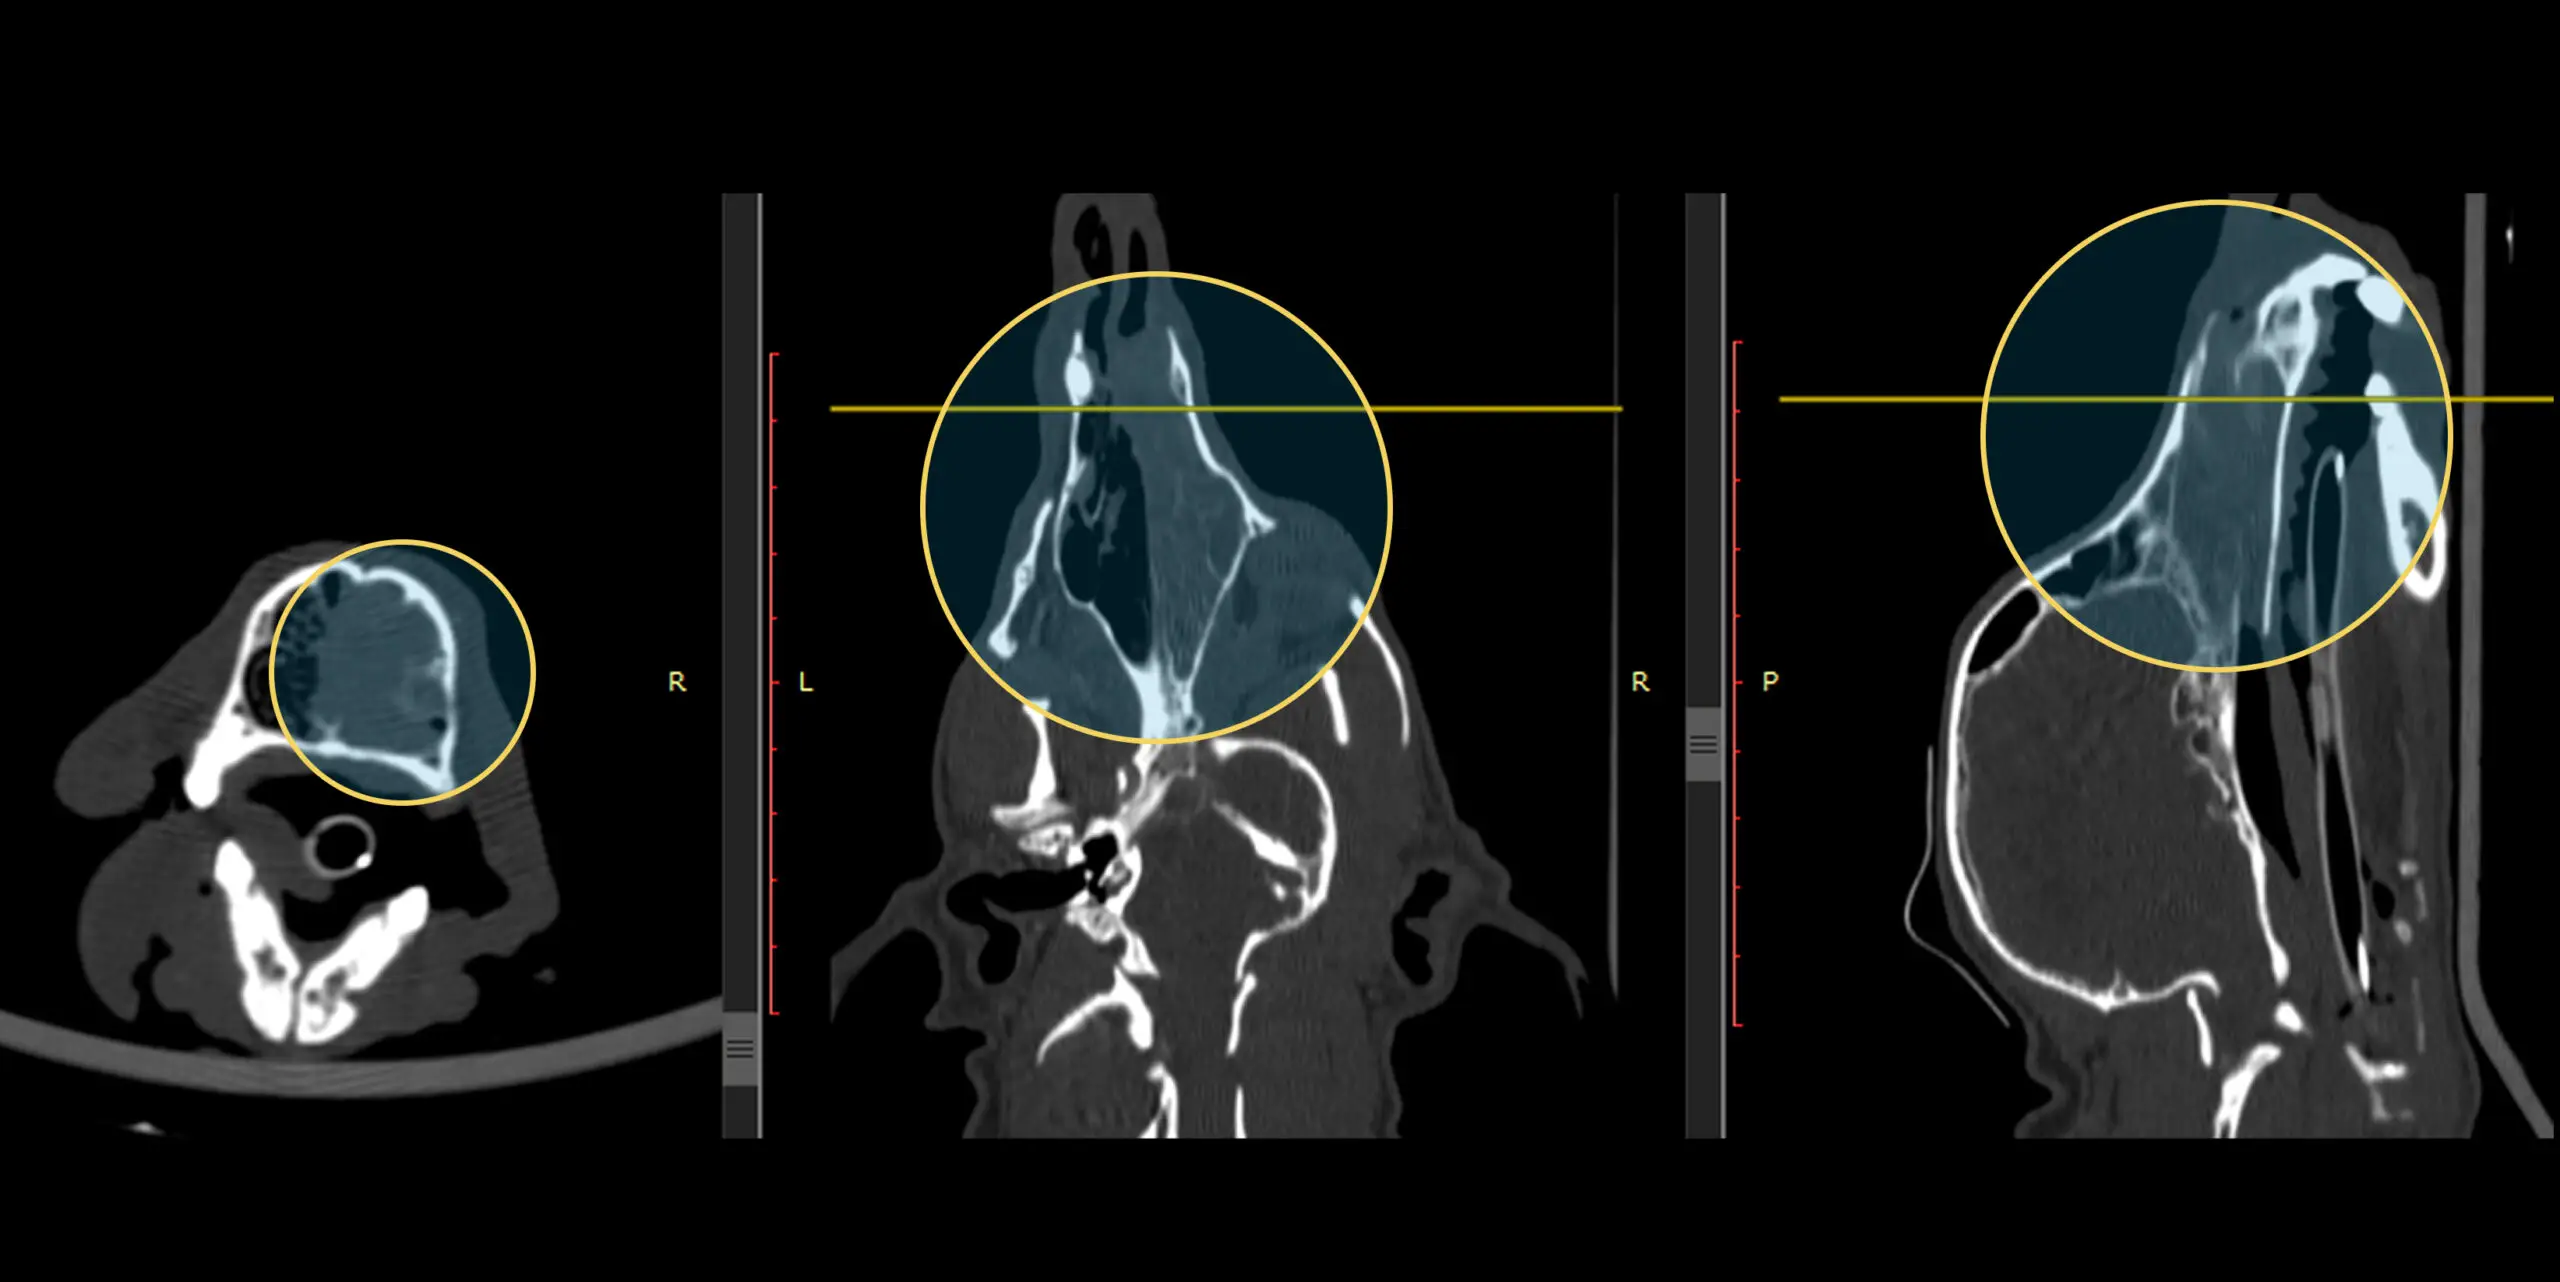

• Especie / Raza / Edad: Canino, Caniche Toy, Hembra, 12 años.

• Localización anatómica: Cavidad nasal.

• Histología tumoral: Carcinoma nasal (Adenocarcinoma).

• Historia clínica: Paciente derivada a interconsulta oncológica tras rinoscopia por secreción nasal sanguinolenta unilateral. La histopatología diagnosticó adenocarcinoma nasal. La TC evidenció ocupación de la cavidad nasal derecha, leve infiltrado en cavidad nasal izquierda y nasofaringe (Estadio II, según clasificación de Adams). Se indicó radioterapia asociada a quimioterapia radiosensibilizante .

• Protocolo de Tratamiento: Dosis total de 36 Gy (6 sesiones de 6 Gy, 2 veces por semana) en concomitancia con Carboplatino (230 mg/m² cada 21 días, 2 ciclos) con intención de disminuir el volumen tumoral y enlentecer la enfermedad .

Resultados: Remisión total de la signología clínica durante 14 meses. Se documentó una respuesta objetiva parcial evaluada 30 días después de finalizar la radioterapia, luego en tomografía de control 12 meses después, se evidenció respuesta completa.

Antes del tratamiento

Después del tratamiento